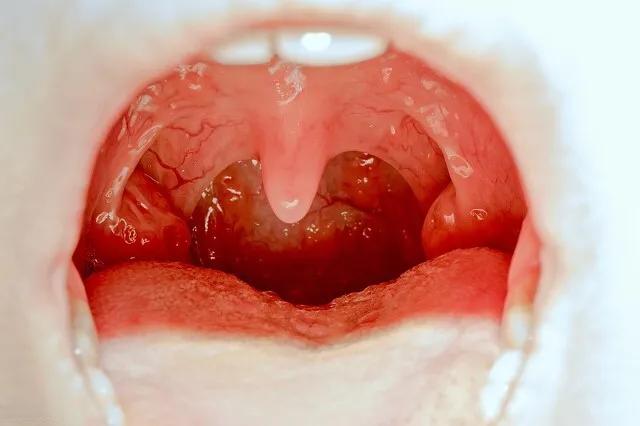

扁桃体手术对许多家长来说是一个艰难的决定。作为人体的重要免疫器官,扁桃体在儿童时期扮演着抵御细菌和病毒的第一道防线。然而,当扁桃体反复发炎或引起其他健康问题时,手术切除可能成为必要的选择。

扁桃体手术的主要适应症包括:一年内扁桃体炎发作7次以上,或连续两年每年发作5次以上,或连续三年每年发作3次以上。此外,扁桃体周围脓肿、扁桃体肥大导致睡眠呼吸暂停综合征等也是手术的指征。值得注意的是,扁桃体手术并非仅限于治疗炎症。在某些情况下,如扁桃体恶性肿瘤或无法控制的扁桃体血管出血,手术也是必要的选择。

关于手术的最佳时机,医学界普遍认为,3岁以下儿童尽量不切除扁桃体,除非病情需要。这是因为低龄期儿童的扁桃体在免疫方面的作用更为重要。4岁以上的儿童,如果符合手术指征,建议进行切除。这是因为7岁以后,扁桃体的功能开始逐渐退化。